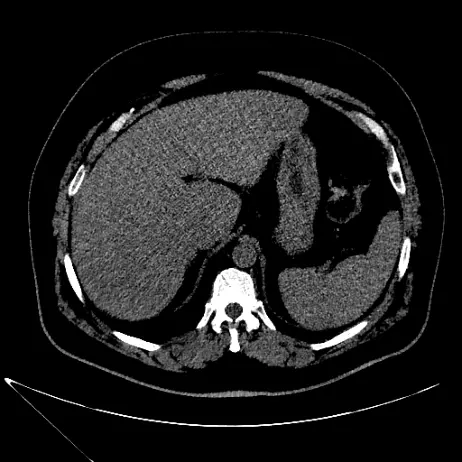

Pre-op

Entraîner des algorithmes pour la prédiction de la zone d'ablation micro-onde dans le traitement du cancer sur des données cliniques réelles

Objectif : Comparer les prédictions des zones d'ablation aux zones d'ablation réelles telles que visible à l'imagerie.

✅ Mise à disposition d'une base de données structurée

✅ Sélection des patients correspondants